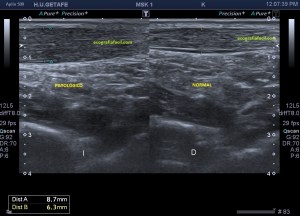

Al explorar la parte interna del muslo, en la zona donde nos señala la paciente encontramos esto…

Rotura

Una imagen de semiología heterogénea que me pareció una rotura fibrilar importante afectando al interior de un músculo de localización interna del que en un primer momento sospeché que podía ser el vasto interno, pero la anatomía no cuadraba, demasiado interno, demasiado cerca de los vasos…

En la imagen 1 observamos la rotura en eje corto, mas flechas rojas señalan el músculo dañado, las amarillas la rotura en si. Observamos la anatomía que la rodea y que es referencia siempre.